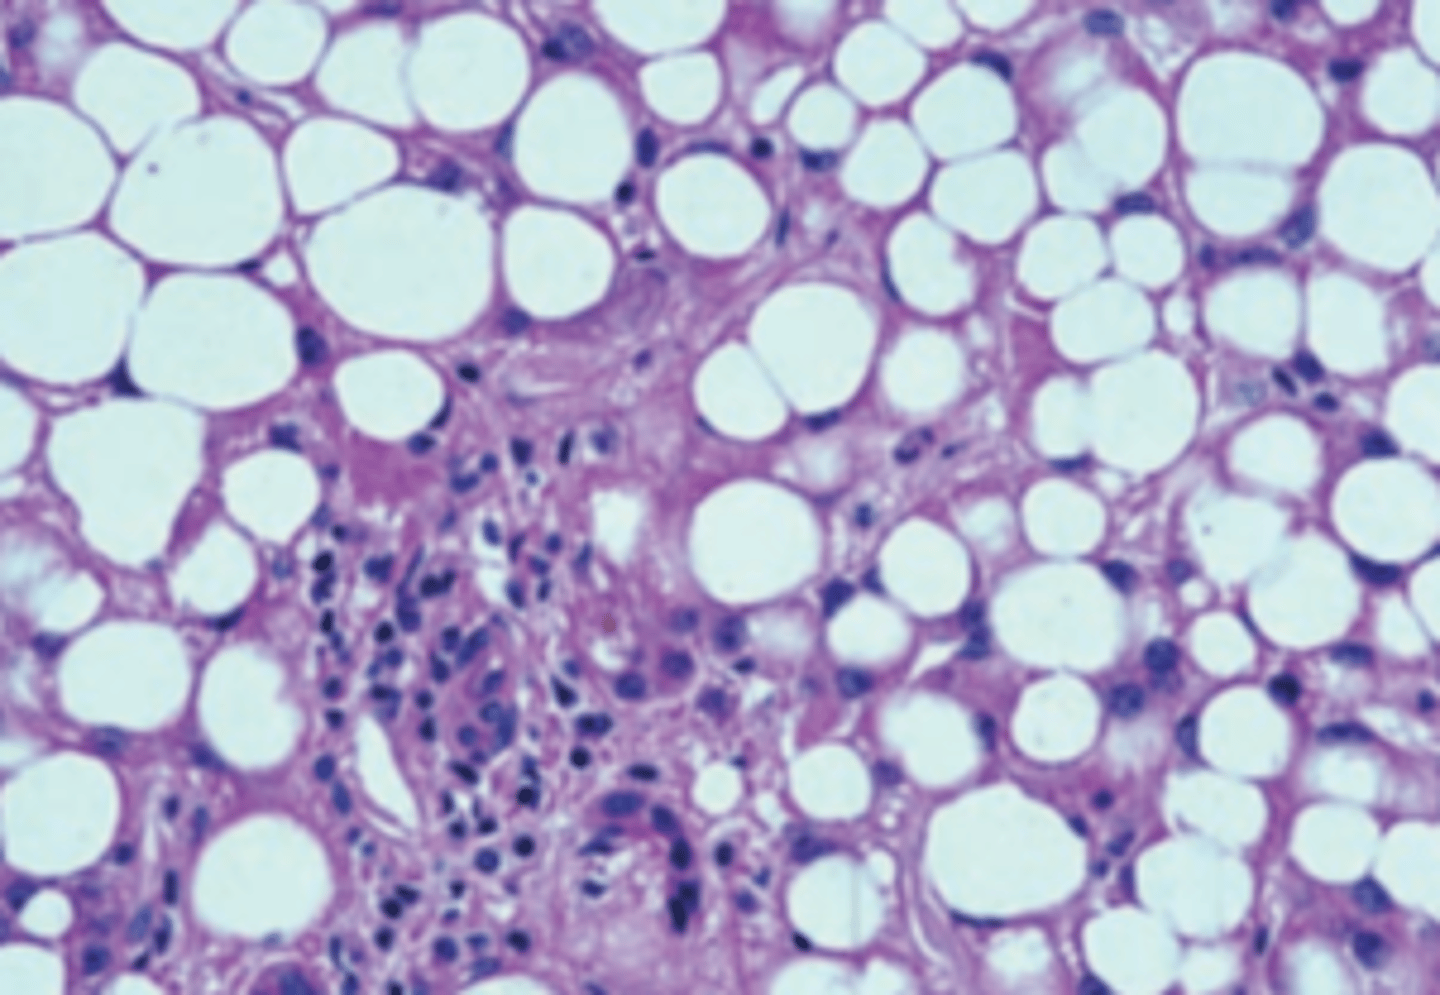

Revert to normal

A 60-year-old man has a 6-month history of abdominal swelling. On a daily basis, he smokes two packs of cigarettes, drinks five cups of coffee, and reports that he consumes 2 sixpacks of beer. Physical examination shows a distended abdomen with a palpable liver 2 cm below the costal margin. A liver biopsy is shown in the image. If this patient becomes abstinent, his liver will most likely do which of the following?

(A) Develop hepatocellular carcinoma

(B) Progress to cirrhosis

(C) Progress to inflammatory hepatitis

(D) Remain unchanged

(E) Revert to normal